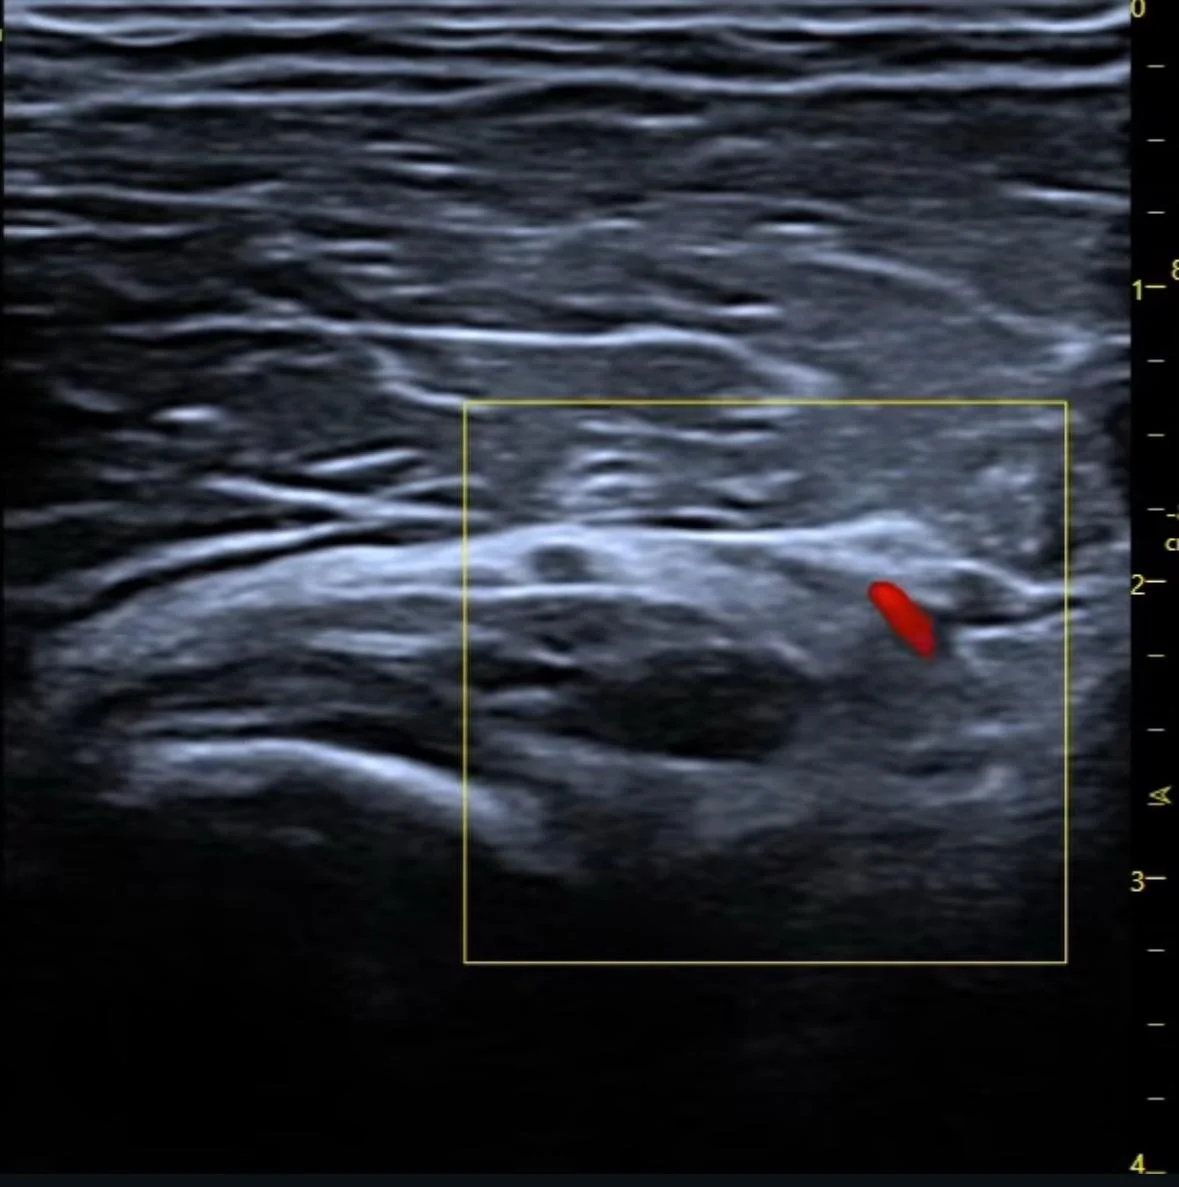

Assessment may also include ultrasound imaging, where appropriate, to assist clinical evaluation of tissue characteristics or product location.

• ultrasound imaging, where appropriate, to assist assessment

• Where appropriate, diagnostic ultrasound may be used to help visualise soft tissue structures, product placement or areas of concern. This imaging can assist the clinician in understanding what is happening beneath the skin and inform recommendations for further management. Not all cases require ultrasound; its use is decided on an individual basis.